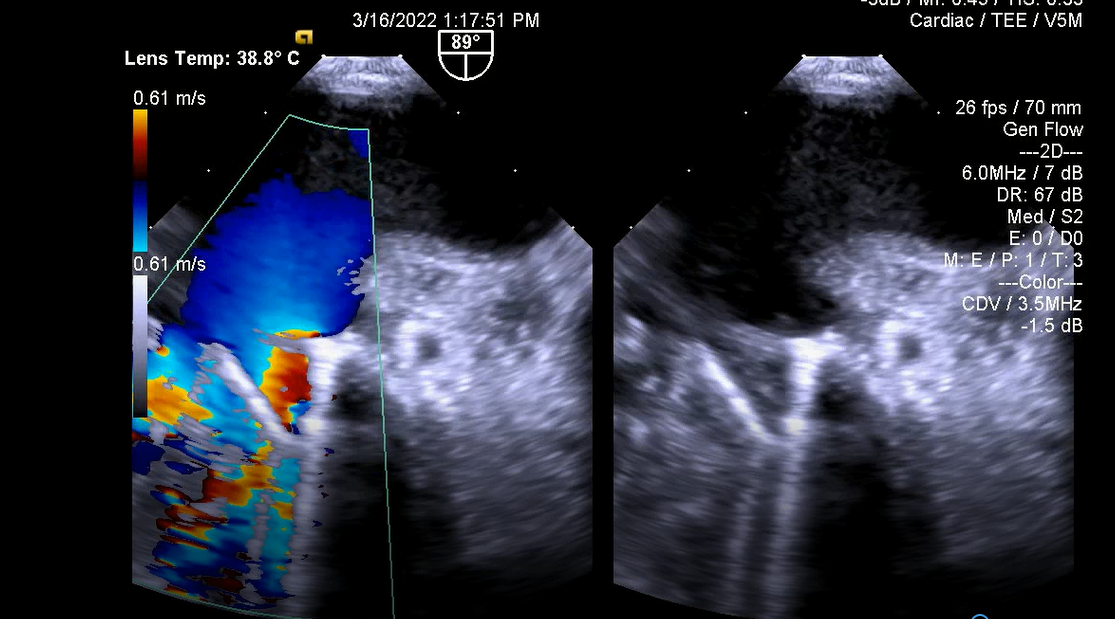

5.Thông liên nhĩ lỗ xoang tĩnh mạch chủ trên

6.Dẫn đường hỗ trợ đóng thông liên nhĩ bằng dụng cụ